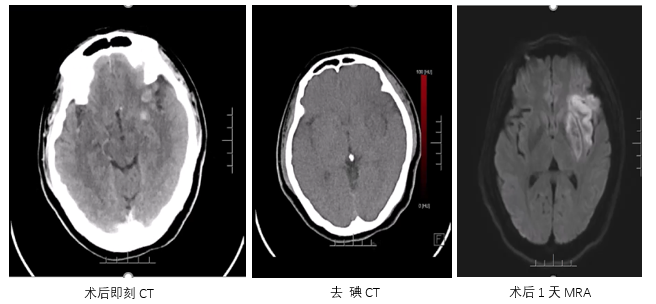

术后评估

病历夹什么径技·第151期|串联营病历夹:京广连营_https://www.jmylbn.com_新闻资讯_第30张

病历夹什么径技·第151期|串联营病历夹:京广连营_https://www.jmylbn.com_新闻资讯_第31张

病历夹什么径技·第151期|串联营病历夹:京广连营_https://www.jmylbn.com_新闻资讯_第32张

病历夹什么径技·第151期|串联营病历夹:京广连营_https://www.jmylbn.com_新闻资讯_第33张

<<滑动查看下一张图片>>

• 术后即刻:去碘CT排除出血风险,梗死灶出现。

• 术后一天:DWI显示梗塞面积没有明显增大,MRA提示血管再通,发现存在LMCA动脉瘤。

• 术后四天:CT显示没有出血表现,梗死灶已经形成。

• 术后3个月:复查CT显示恢复情况良好。